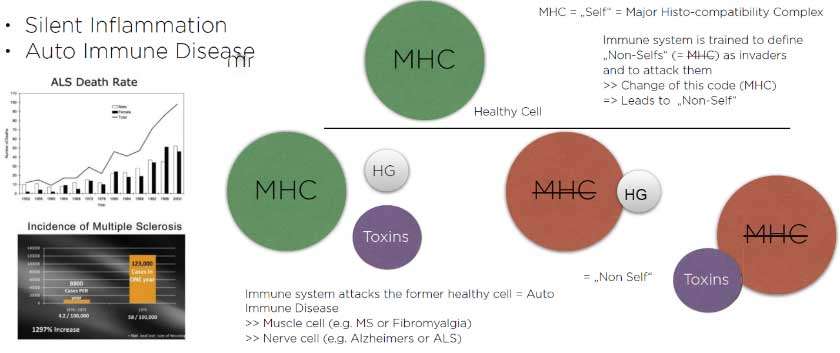

Activation of T cells which are a part of our immune system in systemic inflammatory processes (like- Cancer, Heart disease, Arthritis(substance P), autoimmune diseases, neurodegenearative diseases like parkinsons, and Alzhiemers disease) causing elevated levels of Interleukin-6 (IL-6) and chemokine ligand 5 (CCL5), also known as RANTES (regulated on activation, normal T cell expressed and secreted). Higher the RANTES Score higher the incidence of chronic oxidative stress related diseases.

Silent inflammation due to root canal therapy, cavitation (avascular osteonecrosis) and titanium implants leads to immune system activation. The intraoral interference fields created by metals, NICOs, bacteria in root canal treated teeth produce highly toxic hydrogen sulfides (Thioether/Mercaptan), metals show cytotoxic, immunological and carcinogenic effects and NICOs (Neuralgia inducing osteonecrosis) consist of increased inflammatory mediators like RANTES, FGF-2 and IL-1ra.

One out of two Americans suffer from immune disorders. If we look attentively at the changes occurring in our environment, we will notice some trends running in parallel: an exponential increase in chronic diseases, a similarly exponential trend of increasing strain on our immune system, but also an exponential increase in organic nutritional and behavioral concepts (Figure 1 and Figure 2).

Chronic diseases, such as cancer, ALS, Alzheimer’s disease, Parkinson’s disease, MS, Crohn’s disease and chronic fatigue syndrome, Breast Cancer are increasing at an explosive rate, and extrapolation of the curves shows that within a few years, everyone living in the Western world will be affected by at least one of these diseases.